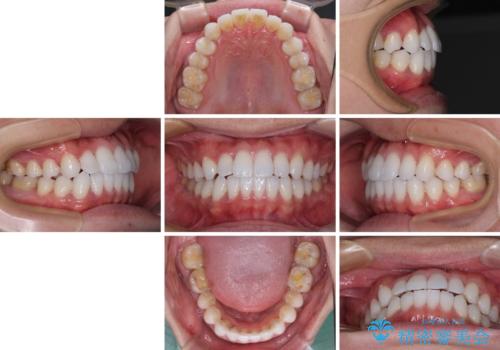

前歯のクロスバイトを改善 インビザラインによる矯正治療

- 前歯のクロスバイトを気にして来院された患者様です。

デコボコやクロスバイトが散見されたため、IPR(歯と歯の間を削る)によってスペースを獲得できるように設計し、インビザラインにより治療を行うこととしました。

今回は、ワイヤー装置を併用することなく治療を行い、トラブルなく、満足のいく歯列に整えることができました。

矯正治療の途中でホームホワイトニングを併用され、術前とは見違えるほどきれいな口元となりました。